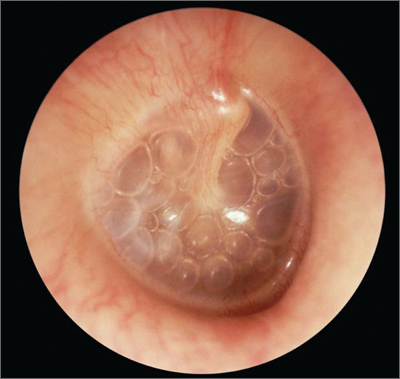

Pathophysiology of cholesteatoma.

A chronically negative middle ear pressure causes the tympanic membrane to retract, forming a retraction pocket. The retraction pocket is lined by squamous, non-keratinising epithelial tissue and releases osteolytic enzymes, allowing the cholesteatoma to grow independently. The osteolytic enzymes can cause local bone erosion, allowing the cholesteatoma to be locally invasive and destructive.

Presentation of cholesteatoma (signs / symptoms)

Symptoms: - vertigo - hearing loss - headache - facial nerve palsy Signs: - conductive hearing loss (progressive) - otorrhoea - otoscopic findings (see image)